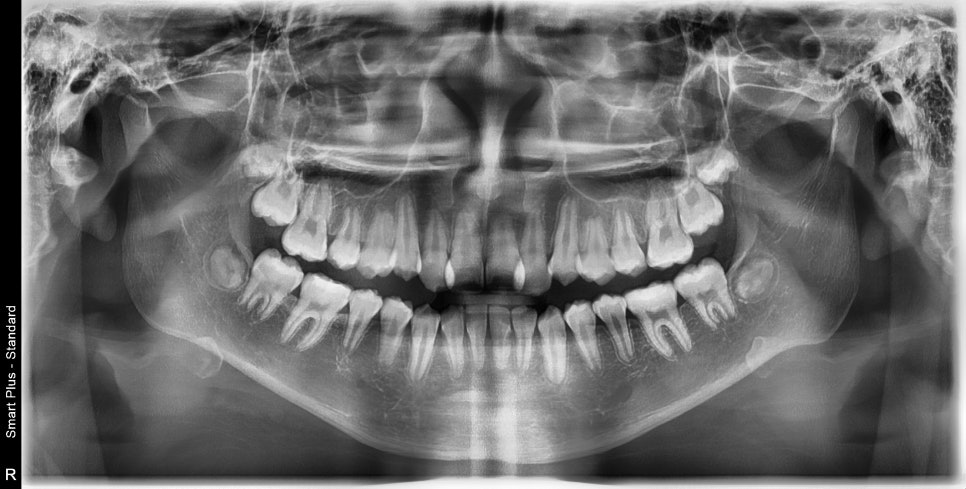

2023.4.18.에 처음 내원해서 23년6월초부터 치료를 시작한 아이입니다.

치료의 마무리는 2024.11.11.에 마무리 했습니다.

약 1년 5개월정도 진행했습니다.

두번째 치아가 덧니로 있는 경우의 치료는 흔한 경우지만

생각보다 많은 노하우가 필요한 치료라고 생각합니다.

교정 치료 중에 화살표 최후방 치아가 맹출하여,

이 치아를 배열하는 과정에서 치료가 조금 더 길어지긴 했습니다

최후방 치아가 나올때 약간 삐뚤게 나옴으로 인해 1회 재제작을 했습니다.